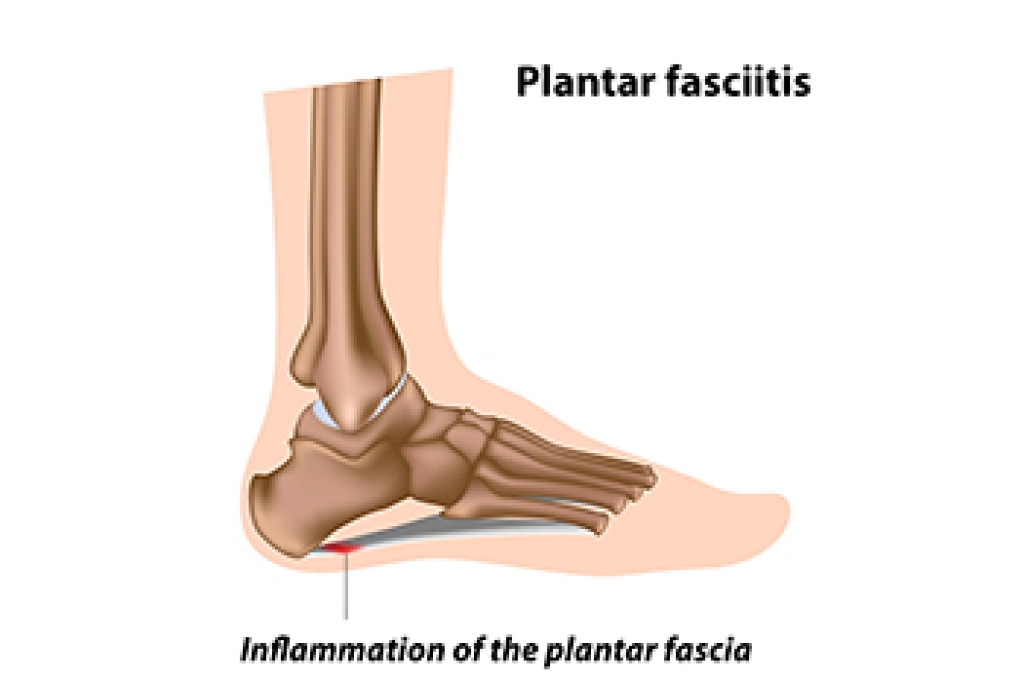

What Can Cause Plantar Fasciitis?

The plantar fascia is a thick band of tissue that connects the heel to the toes. Plantar fasciitis, an inflammation of this tissue, can stem from various biomechanical factors. Problems like an abnormal lower leg structure, limited ankle movement, and inward or outward heel or foot angles can strain the plantar fascia. These abnormalities can alter foot mechanics, leading to excessive tension and micro-tears in the fascia. Symptoms include sharp heel pain, especially after prolonged periods of standing or walking, which tends to improve with rest but worsens upon resuming activity. Early morning stiffness and tenderness in the heel or arch are also common. Addressing these biomechanical issues through proper footwear, orthotics, stretching exercises, and avoiding excessive strain on the feet can help to manage symptoms and prevent recurrence of this ailment. If you have been afflicted by plantar fasciitis, it is suggested that you confer with a podiatrist who can offer you various effective treatment methods.

Plantar fasciitis is a common foot condition that is often caused by a strain injury. If you are experiencing heel pain or symptoms of plantar fasciitis, contact Pasquale Cancelliere, DPM from Candria Foot and Ankle Specialists. Our doctor can provide the care you need to keep you pain-free and on your feet.

What Is Plantar Fasciitis?

Plantar fasciitis is one of the most common causes of heel pain. The plantar fascia is a ligament that connects your heel to the front of your foot. When this ligament becomes inflamed, plantar fasciitis is the result. If you have plantar fasciitis you will have a stabbing pain that usually occurs with your first steps in the morning. As the day progresses and you walk around more, this pain will start to disappear, but it will return after long periods of standing or sitting.

What Causes Plantar Fasciitis?

- Excessive running

- Having high arches in your feet

- Other foot issues such as flat feet

- Pregnancy (due to the sudden weight gain)

- Being on your feet very often

There are some risk factors that may make you more likely to develop plantar fasciitis compared to others. The condition most commonly affects adults between the ages of 40 and 60. It also tends to affect people who are obese because the extra pounds result in extra stress being placed on the plantar fascia.